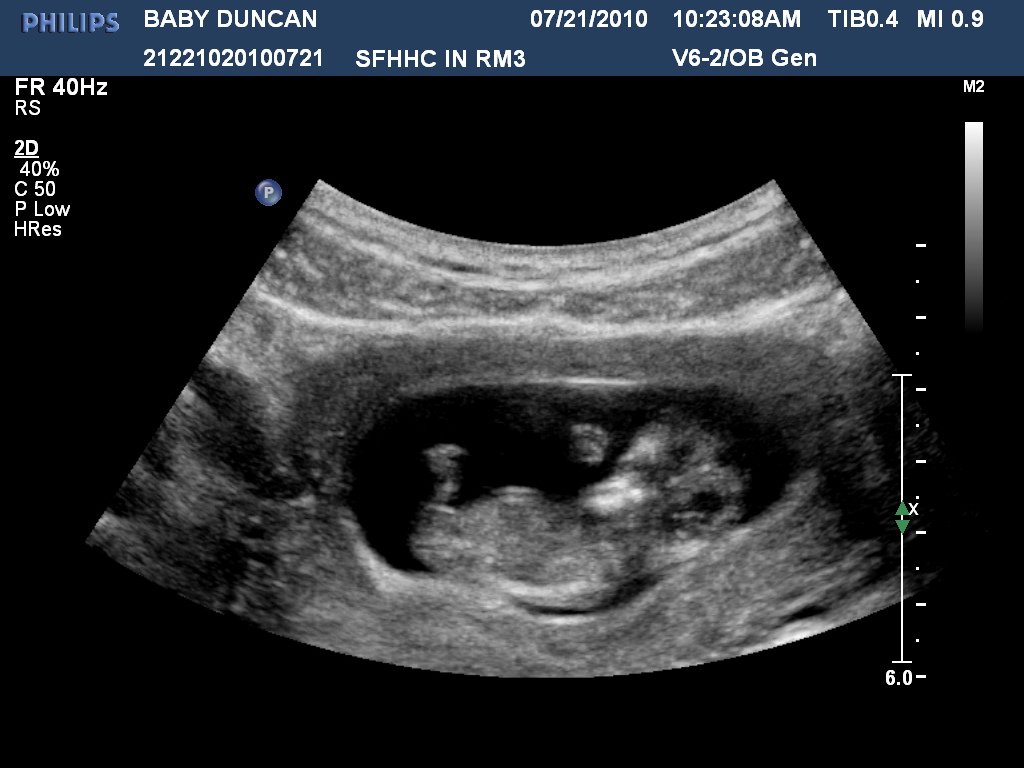

Along with developing sleeping and waking cycles, he or she is growing more into what your newborn will look like at birth. All your baby�s organs form during the embryo stage. Perhaps the trickiest part of reading your own ultrasound is being able to locate the nub. This ultrasound image shows the fetal head, arms, abdomen, and legs at 11 weeks. An ultrasound at this gestational age will help confirm your due date, and it is part of the early risk assessment testing (era) for a chromosomal abnormality, such as down syndrome. Now, in the fetal stage, your baby�s organ systems will grow and mature until birth.

Does anyone have ultrasound pictures from 10 or 11 weeks they�d like to share? At this stage, the baby has put on some weight and filled out to make features more visible, yet still enough fluid in front of baby’s face to obtain great images. 38 weeks. This ultrasound image shows the fetal head, arms, abdomen, and legs at 11 weeks. While your healthcare provider counts these two weeks toward your due date, you aren�t really pregnant. Not sure if you can see the gender (we don’t want to find out until birth) hope that.

:) also, can you see the baby move around on the ultrasound at this stage? This ultrasound image shows the fetal head, arms, abdomen, and legs at 11 weeks. Above is a picture of what his or her legs look like. Purpose of the 11 week ultrasound scan. Now, in the fetal stage, your baby�s organ systems will grow and mature until birth.